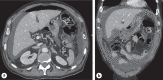

Duodenal perforation is rare and associated with a high mortality. Therapeutic strategies to address duodenal perforation include conservative, surgical, and endoscopic measures. Surgery remains the gold standard. However, endoscopic management is gaining ground mostly with the use of over-the-scope clips and vacuum-sponge therapy. A 67-year-old male patient was admitted to the emergency room for persistent epigastric pain, melena, and signs of sepsis. The physical assessment revealed reduced bowel sounds, involuntary guarding, and rebound tenderness in the upper abdominal quadrant. A contrast-enhanced computed tomography (CT) scan confirmed the suspicion of ulcer perforation. The initial laparoscopic surgical approach required conversion to laparotomy with overstitching of the perforation. In the postoperative course, the patient developed signs of increased inflammation and dyspnea. A CT scan and an endoscopy revealed a postoperative leakage and pneumonia. We placed an endoscopic duodenal intraluminal vacuum-sponge therapy with endoscopic negative pressure for 21 days. The leakage healed and the patient was discharged. Most experience in endoscopic vacuum-sponge therapy for gastrointestinal perforations has been gained in the area of esophageal and rectal transmural defects, whereas only few reports have described its use in duodenal perforations. In our case, the need for further surgical management could be avoided in a patient with multiple comorbidities and a reduced clinical status. Moreover, the pull-through technique via PEG for sponge placement reduces the intraluminal distance of the Eso-Sponge tube by shortcutting the length of the esophagus, thus decreasing the risk of dislocation and increasing the chance of successful treatment.